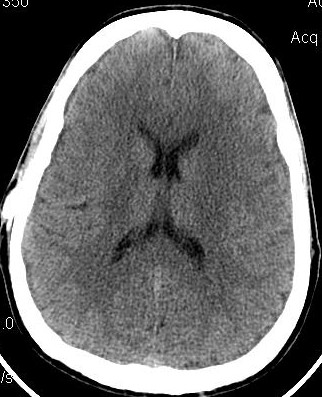

Below, are my CT images beginning on Jan. 17, 2011, where there is enlargement of the ventricles, followed by further enlargement on April 9, 2011, and what appears to be more enlargement on June 8, 2011, despite my May 23, 2011 revision. Then, there appears to be a slight decrease in ventricular enlargement on June 20, 2011, followed by normal size (almost too small) ventricles on July 23, 2011. We felt my ventricles came down in size too quickly, and began to raise the proGav setting over a period of two months, eventually up to 6, and rescanned me on Sept. 15, 2011. Those results indicated my ventricular enlargement had returned, so the proGav was returned to a lower setting of 2.

In hindsight, perhaps one mis-step we made was in not obtaining a CT scan right before surgery so as to have a true baseline. My headache, nausea, memory, and balance symptoms had worsened from April 9, 2011 to May 23, 2011, and I had lost appetite and weight. A CT on the revision date would have likely shown considerably more ventricular enlargement as compared to April 9th, rendering the post op CT of June 8, 2011, an improvement, instead of a worsening as we thought. I was having ongoing headaches upon waking in the a.m. and during the daytime after the proGAV revision, with no improvement in memory, and no apparent improvement on CT compared to April 9th, and requested that the proGAV to be lowered all the way to 0 only a few weeks post op. Despite programmable shunts having been in use since 1999, there still remains some considerable confusion and miscalculation in achieving the most optimal settings, and I remain dissatisfied with industry's inattentiveness to this issue. I also think this lack of attentiveness speaks to the high number of unofficial reports of accidental reprogramming of (Codman & Medtronic) programmable shunts. Of course, with the addition of a locking pin on the proGAV valve, this is unlikely to be an issue.

Under my CT images below, I list each of the proGAV's corresponding settings. It was initially set at 10 during surgery, with no improvement in complaints after one week, I asked that it be lowered to 7, and one week later to 5, then to 3, and finally to 0. During this period, almost every morning I awoke with a substantial headache that I assumed was due to increased ICP and underdrainage. On the June 20, 2011, CT we could finally see some decrease in the dilation of my ventricles, and determined the shunt to be working. But, we were still puzzled by the ongoing awaking a.m. headaches. For this reason, it was temporarily raised to a setting of 2, and then with no relief back down to 0. It remained at 0 for almost a month when the July 23, 2011 scan revealed normal sized ventricles.  Because of the relatively short period it took for my ventricles to come back to normal, we raised the proGAV gradually to 6, and back down to 2 after the Sept. 15, 2011 scan showed a return of ventriculomegaly.

Jan 17, 2011 OSVII                    April 9, 2011 OSVII                 Shunt Revision to proGAV May 23, 2011

June 8, 2011 proGAV  5/20    June 20, 2011 proGAV 3/20      July 23, 2011 proGAV 0/20    Sept. 15, 2011 proGav 6/20   Feb. 1, 2012 proGav 0/20